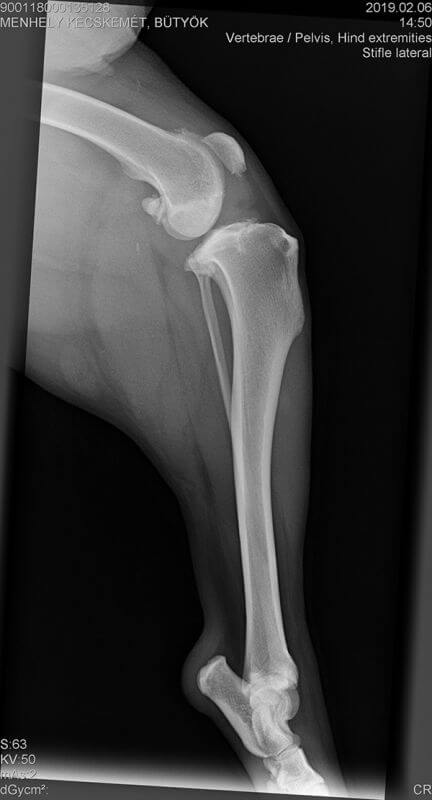

Zu allem Unglück leidet Bütyök an einem alten Kreuzbandriss und Arthrose im Knie. Das Kreuzband wird am 21.2.19 in Budapest operiert.